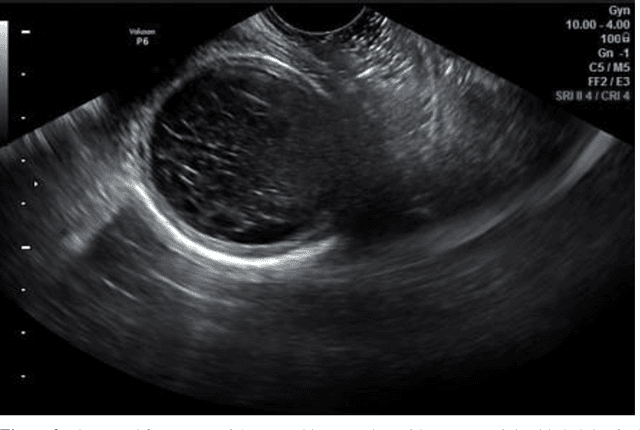

Background, For the purpose of determining the appropriate course of therapy to maintain fertility, a correct diagnosis of ovarian cysts is crucial. Objective, To contrast the results of magnetic resonance imaging and ultrasonography in individuals with ovarian cysts . Methods: research was carried out in the radiology division of Al-Hilla General Teaching hospital and Marjan Teaching Hospital in province Babil in the period of November 2023 and march 2024, Seventy-five Following a physical and ultrasonography examination, the female patient was assessed using magnetic resonance imaging. Women in the over-18 age group exhibit a range of symptoms, such as irregular menstruation, abdominal pain, sensoria, and menorrhagia. Results: Adnexal lesions on US imaging included chocolate cysts (14.6%), dermoid cysts (13.8%), hemorrhagic cysts (HC) (11.6%), simple cysts (32.4%), complicated cysts (21.2%), and multilocular cysts (MC) (6.4%).Simple cysts (SC) made up 29%, complex cysts (6.9%), dermoid cysts (10.9%), chocolate cysts (19.1%), hemorrhagic cysts (HC) 11.3%, multilocular cysts (6.8%), and malignant cysts (MC) 16% of the adnexal lesions on MRI. The USG results show 100% sensitivity, 78.3% specificity, and 89.3% accuracy when compared to the MRI results. Conclusions: Magnetic resonance imaging, which is quite accurate in determining the mass's origin and characterizing its tissue content, may be beneficial in further evaluating monographically vague ovarian cysts with solid or complicated content